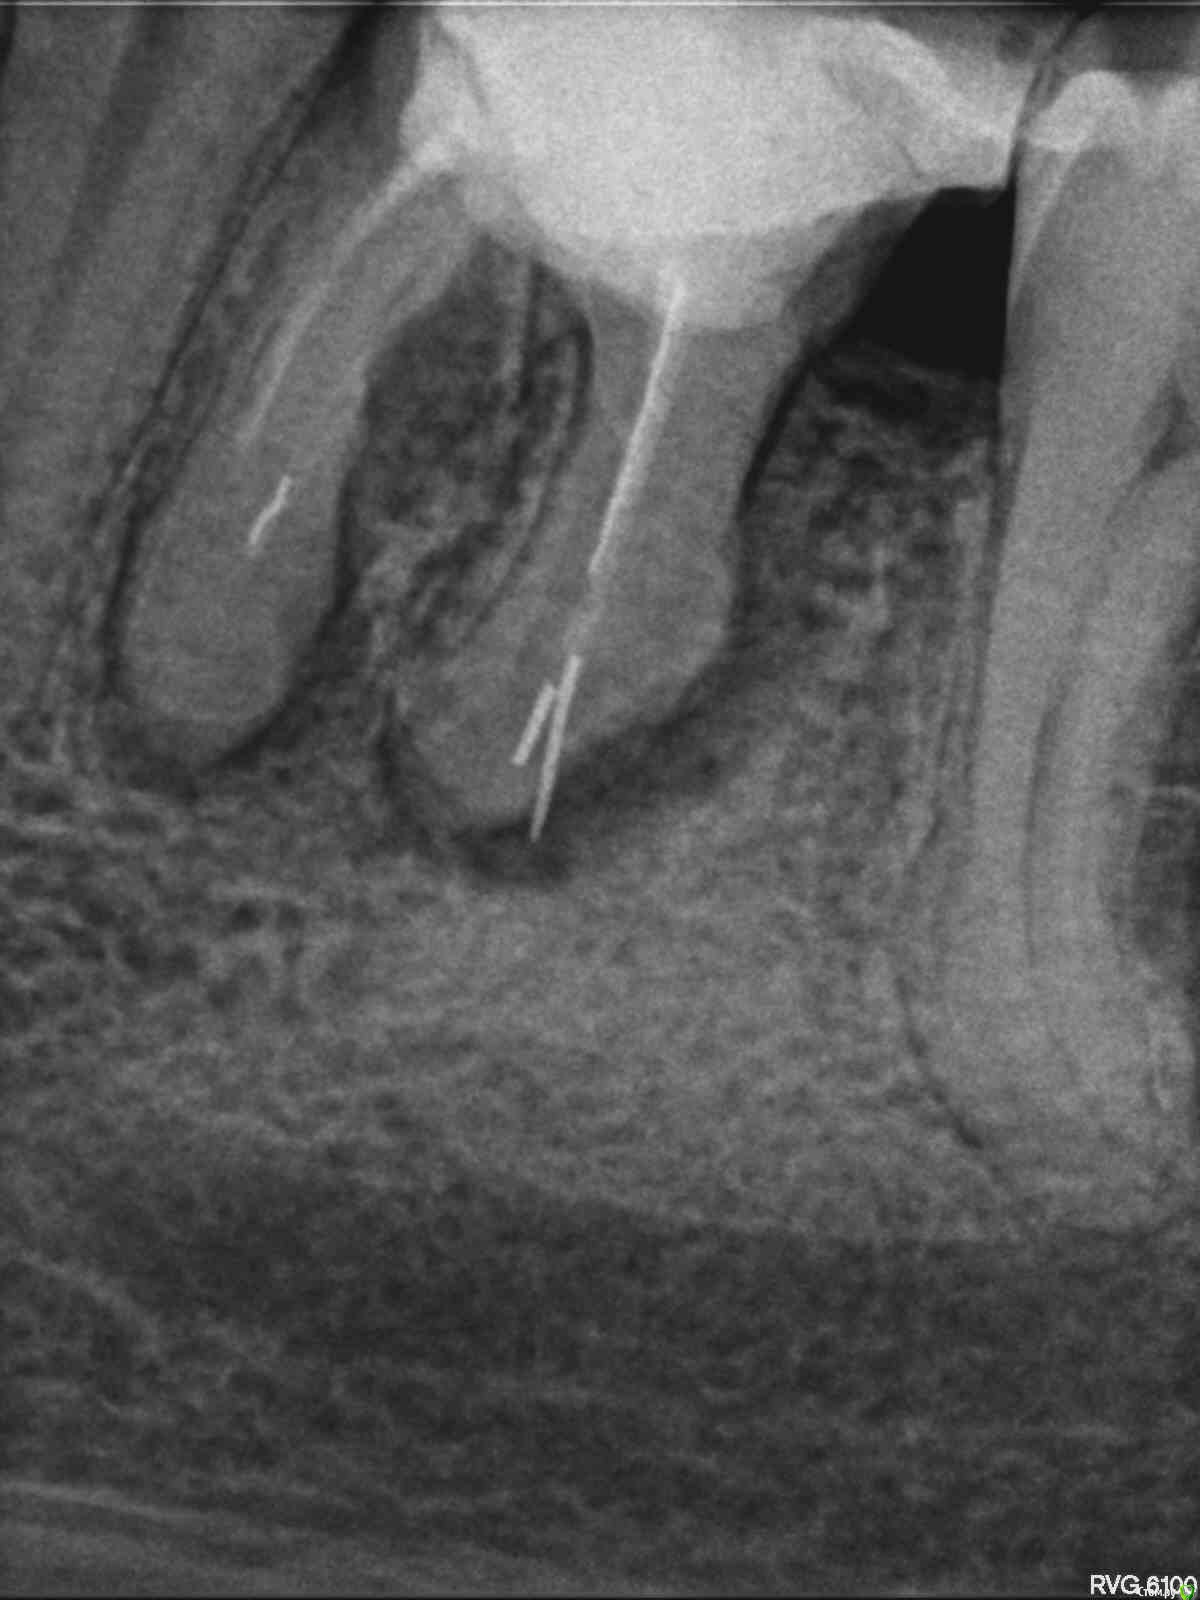

Ладонина Опубликовано 12 декабря, 2017 Поделиться Опубликовано 12 декабря, 2017 (изменено) Здравствуйте, зубы 1.6 и 3.6 в результате плохого лечения имеют кисты больших размеров. На деснах появились свищи. Киста верхнего зуба находиться в верхнечелюстной пазухе. Как быть и что делать? Удалять не хочу, только лечить или удалить кисты без удаления зубов.Зубы не болят.Scan.1.pdf Изменено 12 декабря, 2017 пользователем Ладонина 1 Ссылка на комментарий